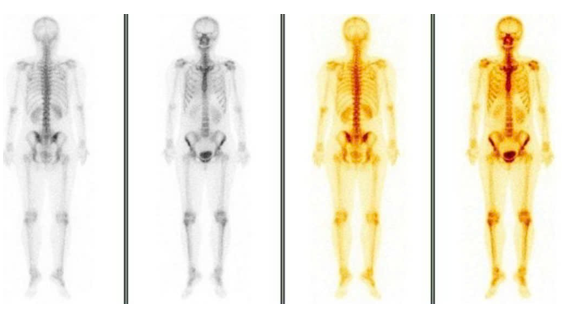

- Xạ hình xương (Tháng 04/2025): chưa phát hiện bất thường

Hình 7: Xạ hình xương chưa phát hiện bất thường